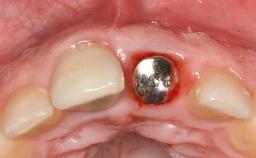

Treatment of Advanced Peri-Implantitis by Implant Removal Followed by Bone Reconstruction and New Implant Placement

Paolo Casentini and Matteo Chiapasco present a case in which the peri-implant defect was not suitable for a fully regenerative approach. It involves implant removal, use of a CAD/CAM customized titanium mesh in the grafting phase, and placement of new implants. A 62-year-old woman was referred for consultation regarding her implant-supported prosthesis replacing teeth 14 to 16. The patient’s main concern was pain and recurrent swelling in the right posterior maxilla. The patient also reported difficulty and discomfort when brushing the area. The patient reported she had been treated in another country, where she had received three implants in combination with sinus-floor augmentation for the replacement of the posterior maxillary teeth three years earlier. The patient indicated “endodontic complications” to be the reason for the extraction of the teeth.